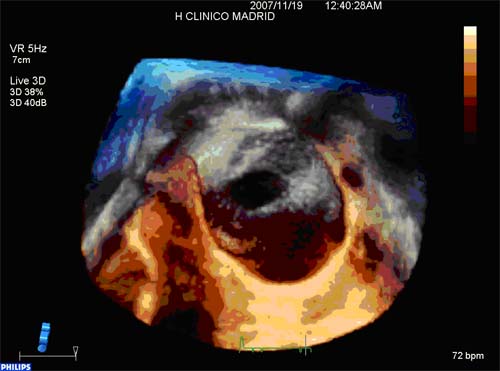

3d Tee Aortic Valve

New Three Dimensional Rendering Image Of Transoesophageal